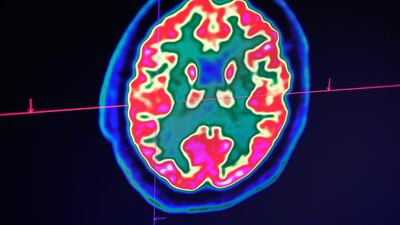

We are more than our brains, but failing to prioritise brain health has dramatic individual and societal consequences. It’s time for everyone to embrace what experts have been repeating for years: there is no health without brain health. That is why the brain matters more than ever in Davos.